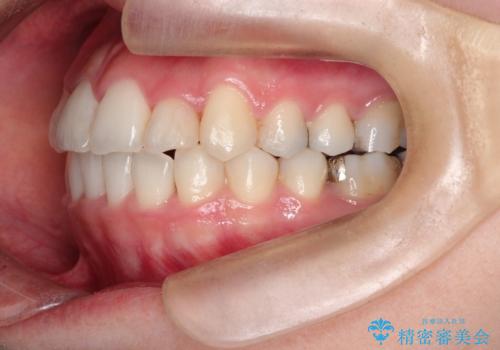

【ワイヤー矯正】前歯の凸凹を非抜歯で治療

- 前歯の凸凹を主訴に来院されました。

側方拡大にてスペースを作ることにより綺麗に前歯を並べることができました。

前歯の凸凹がある場合は治療計画を立てる上でスペースをどのように作るかが重要になります。

今回の場合は主に側方拡大でスペースの確保を行いました。